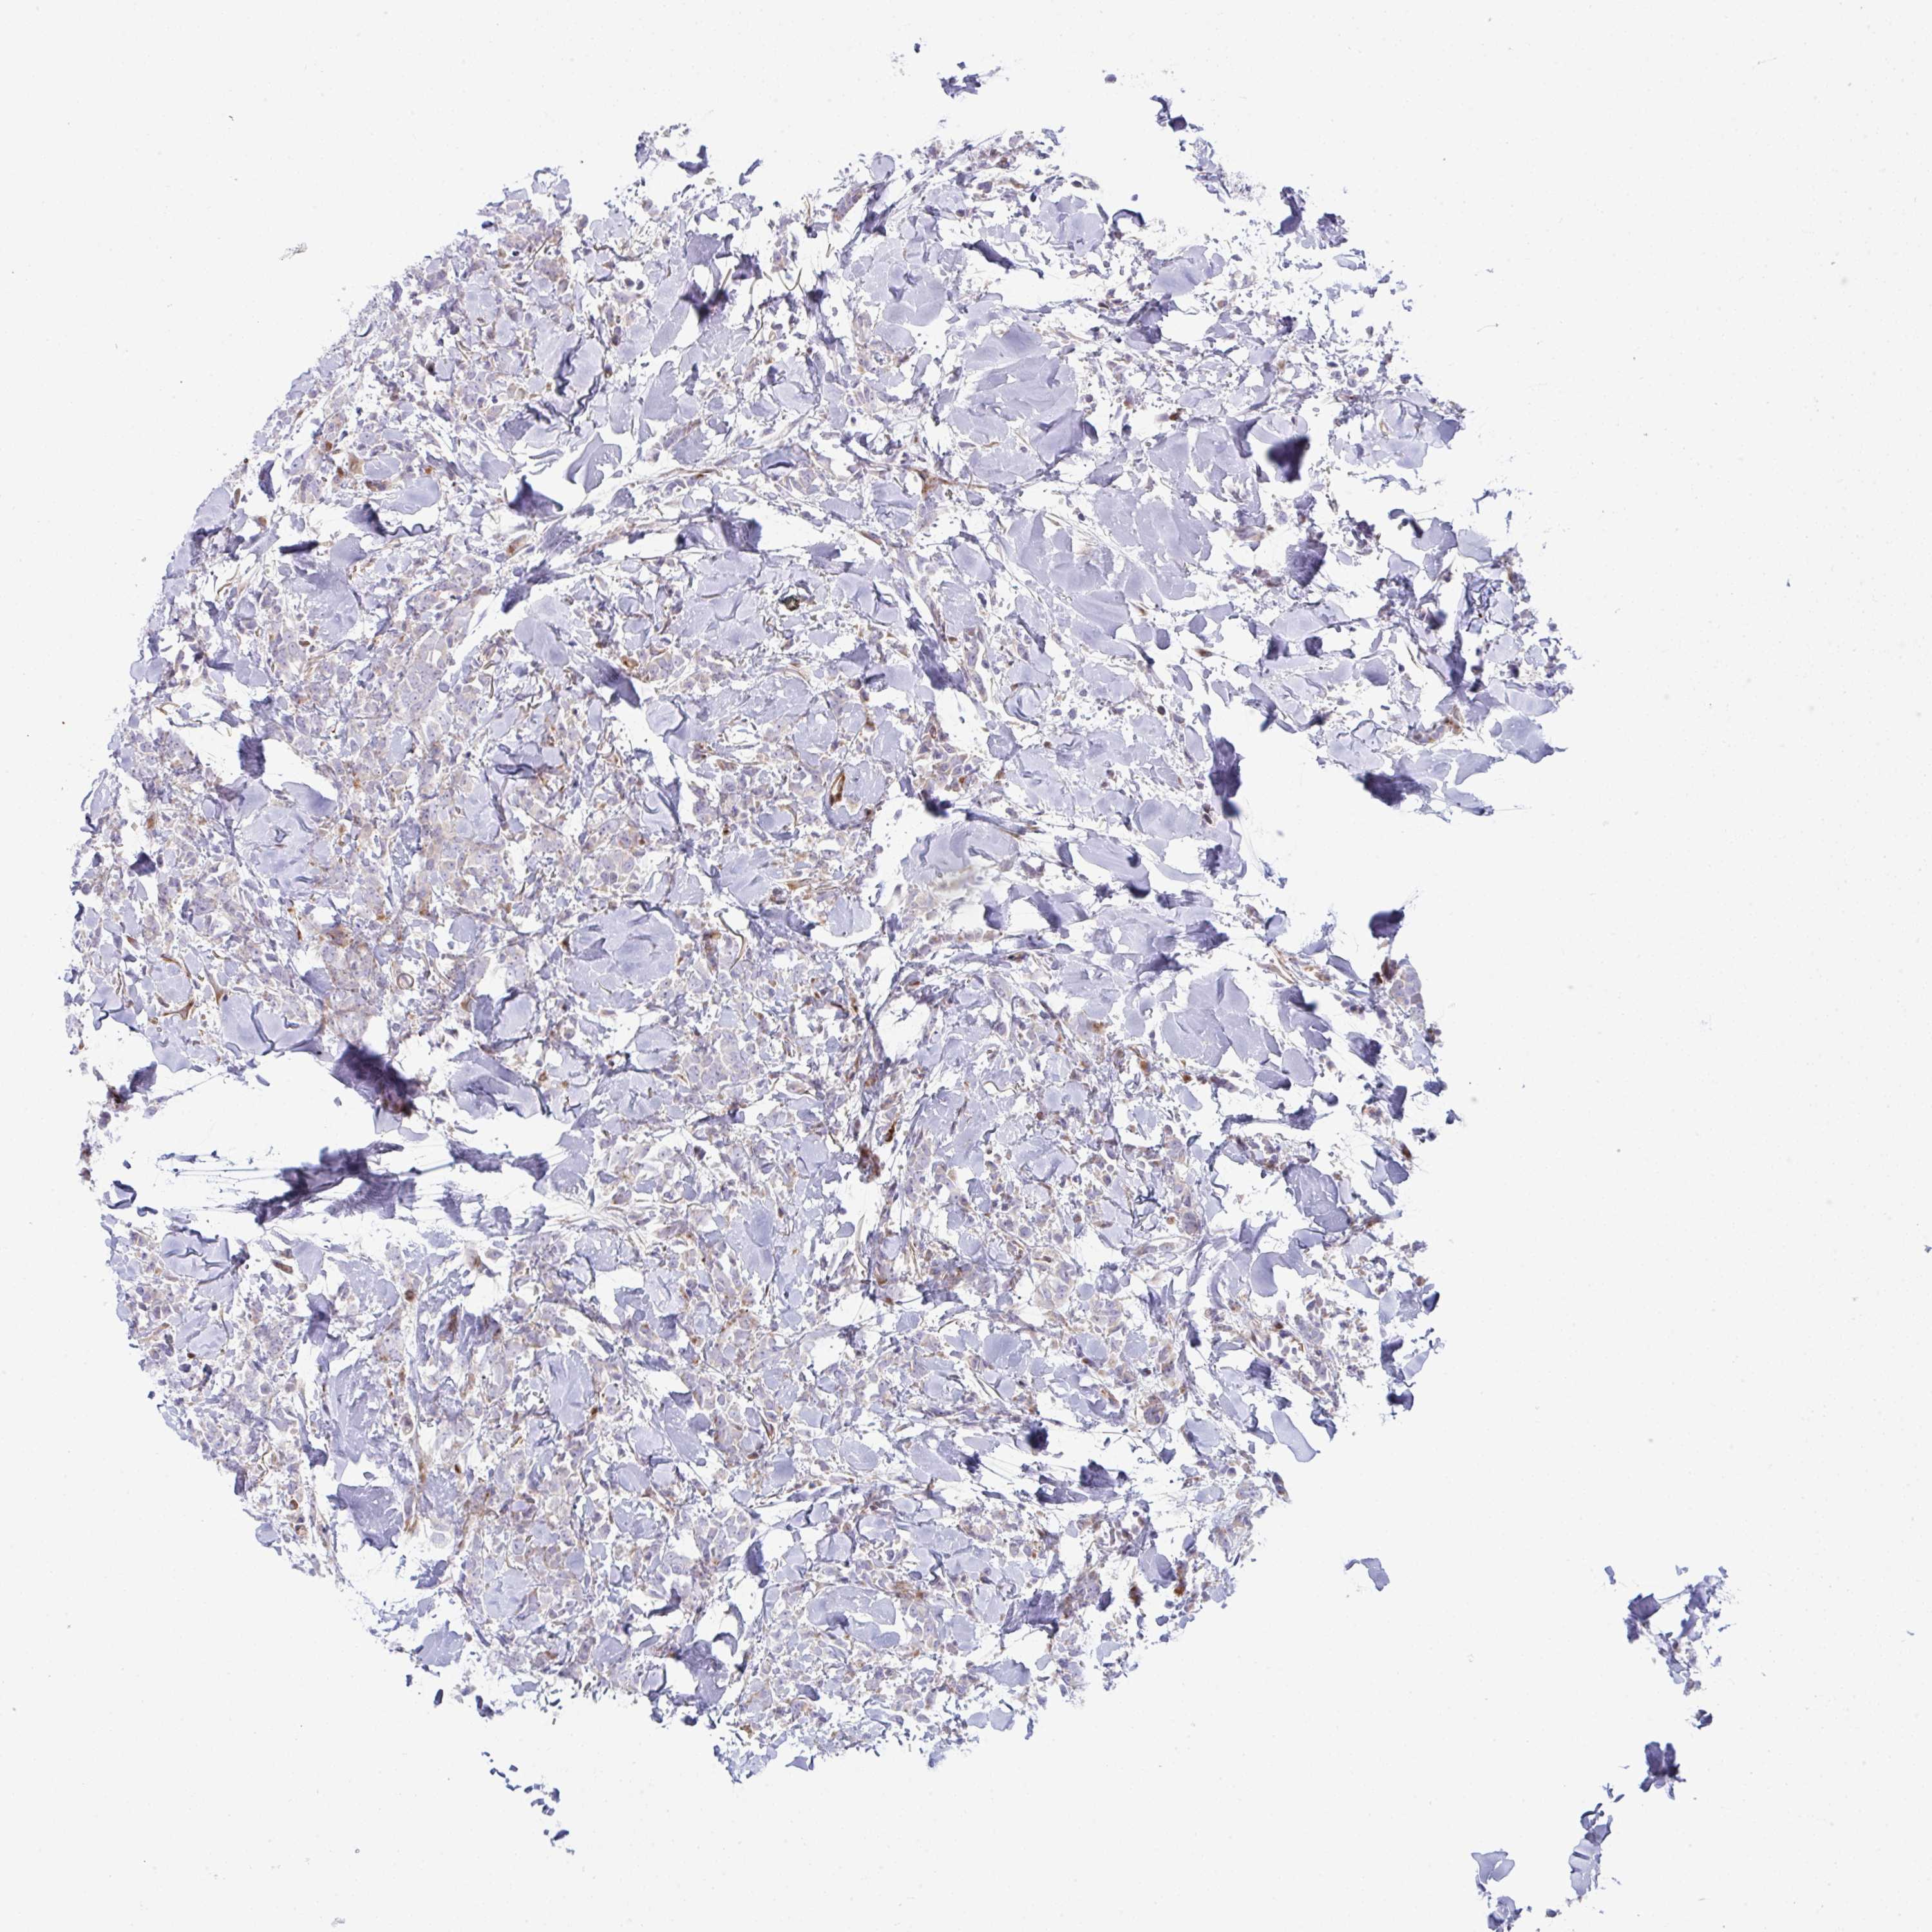

CANCER BREAST CANCER Show tissue menu

BRCA TCGA BRCA VALIDATION PROTEIN EXPRESSION

ANTIBODIES

AND

VALIDATION